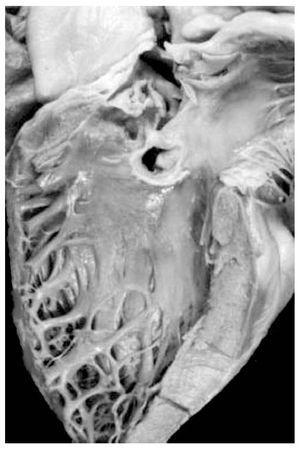

Atrio-ventricular connection: Ventricles are recognized by the trabecular septum's anatomic features. The right ventricle (Figure 3) has a trabecular septum with very thick muscular bands and it also has a structure, the moderator band, inserted in the interventricular septum and in the free wall of the right ventricle, whereas the left ventricle has a trabecular septum with very thin muscular bands in the apical section and it is smooth in the upper section (Figure 4). The former has a group of papillary muscles inserted in the free wall, and the latter has two groups of papillary muscles which are also inserted in the free ventricular wall. Trabecules provide a cavernous-type inner morphological appearance to the right ventricle, whereas the left ventricle has an areolar appearance.

Figure 4. Internal morphology of the left ventricle.